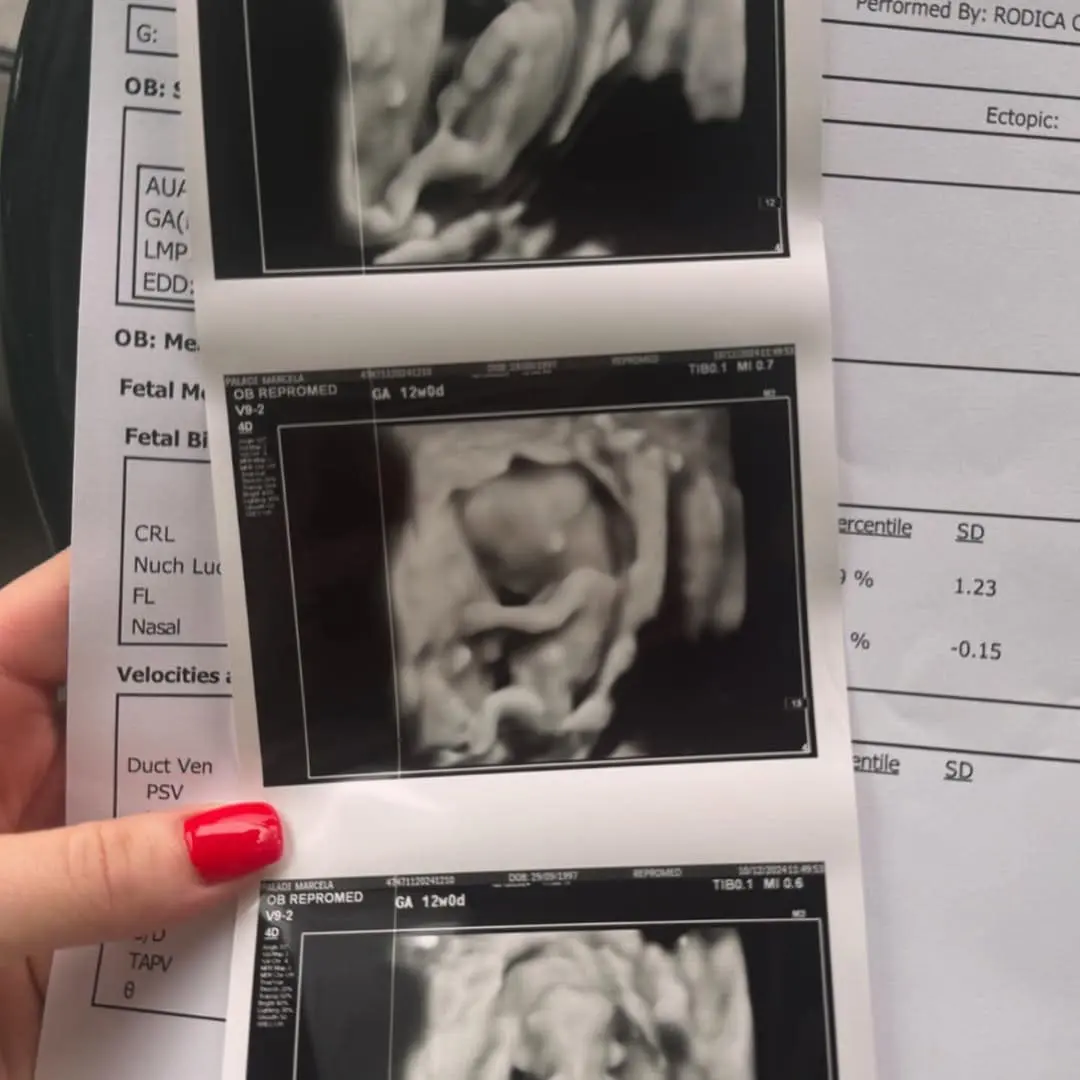

Își imagina că va duce cele nouă luni de sarcină pe proteze, dar a fost nevoită să revină în scaunul cu rotile. Marcela Paladi, tânăra care și-a pierdut picioarele într-un accident cumplit pe viaductul din Chișinău și care acum e însărcinată a povestit în cadrul emisiunii „Iubește viața” despre jertfa pe care a făcut-o când a aflat că e însărcinată.

Tânăra practic a renunțat la picioare, la mersul independent, care a devenit posibil datorită protezelor, ca să-și păzească copilul. Medicii au atenționat-o că fătul ar putea fi în mare pericol, dacă mama cade de la înălțimea protezelor.

„Eram pregătită că o să fiu gravidă pe proteze, dar vorbind cu medicii noștri, consultându-mă, am înțeles că nu e chiar așa, riscul este foarte mare, dacă sunt proteze și cad. E una când cazi fără copil în tine, te lovești și trece, în cazul meu puteam să am pierdere. Am avut de ales: sau moftul meu de a merge, într-un moment asta a fost un moft, nu o nevoie, sau mă jertfesc pentru copil. Evident am ales a doua. O să fie timpul și pentru proteze, ele stau în dulap, cumincioare, mă așteaptă pe mine”, a spus Marcela.